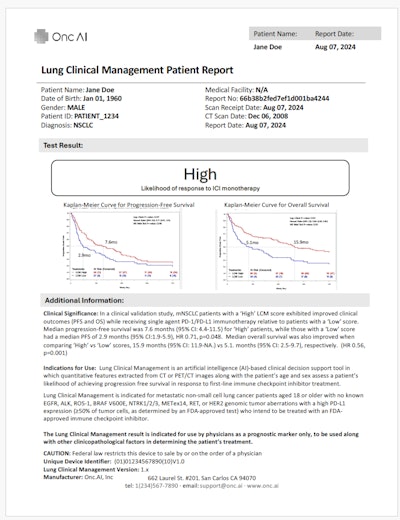

Onc.ai

Onc.AI is a Series-A funded company that’s developing imaging AI models for predicting clinical outcomes in cancer patients, initially focusing on metastatic lung cancer.

The firm sells models directly to pharmaceutical companies such as Pfizer, GSK, and Amgen to inform drug development. It is also developing clinical models intended for medical oncology decision support.

AI predictions for treatment response in metastatic lung cancer patients are provided in a PDF format.Onc.ai

AI predictions for treatment response in metastatic lung cancer patients are provided in a PDF format.Onc.ai

“Although our AI models are solely based on a cancer patient’s CT or PET/CT scan, our main user is the medical oncologist,” said Akshay Nanduri, founder and CEO.

In January, Onc.ai received a breakthrough device designation from the U.S. Food and Drug Administration for its Onclara model for metastatic lung cancer; the software was previously known as Serial CT Response Score. The company hopes its first models will be cleared for marketing authorization as software-as-a-medical device (SaMD) decision-support software in the second half of 2026.